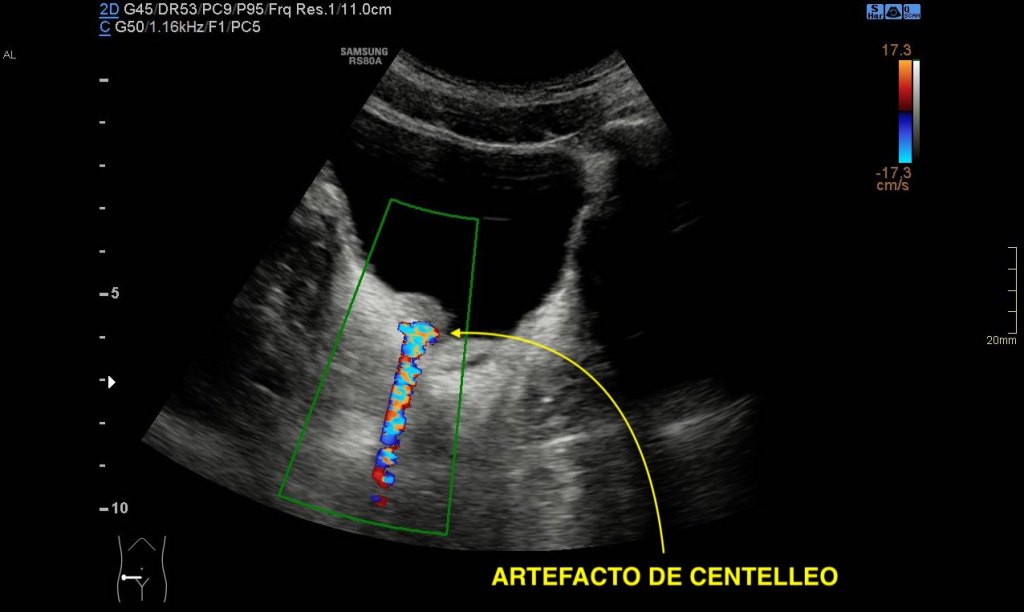

- Con Doppler se observa el artefacto o efecto de centelleo:

- El efecto de centelleo (o «twinkling artifact») en el contexto del ultrasonido Doppler, especialmente en relación con una litiasis yuxtavesical, es un fenómeno interesante. Este efecto se observa a menudo en la ecografía Doppler cuando se evalúan cálculos (piedras) en el tracto urinario, incluidos los que se encuentran cerca de la vejiga (yuxtavesicales).

- Definición: El efecto de centelleo es un artefacto de color observado en el ultrasonido Doppler, que aparece como una rápida fluctuación de colores detrás de un objeto sólido, como un cálculo.

- Apariencia: Se manifiesta como un mosaico de colores brillantes (rojos y azules) en el Doppler a color, detrás del cálculo.Es una lectura incoherente del Doppler.

- Causa del Efecto de Centelleo:

- Reflexión de la Onda Ultrasónica: Se cree que el efecto se debe a la reflexión y refracción de las ondas ultrasónicas en la superficie irregular del cálculo, lo que provoca cambios en la fase y frecuencia de las ondas reflejadas.

- Composición y Superficie del Cálculo: Los cálculos con superficies rugosas o irregulares tienden a producir un efecto de centelleo más pronunciado.

- Importancia Clínica en Litiasis Yuxtavesical:

- Identificación de Cálculos: El efecto de centelleo puede ayudar a identificar cálculos en la región yuxtavesical, especialmente en casos donde la imagen en escala de grises no es concluyente.

- Diferenciación de Otras Patologías: Ayuda a diferenciar cálculos de otras estructuras o patologías en el área de la vejiga.

- Localización: Facilita la localización exacta del cálculo, lo cual es importante para el tratamiento y manejo.

- Limitaciones:

- No Específico: Aunque el efecto de centelleo es un indicador útil, no es específico para cálculos y puede ocurrir con otras estructuras.

- Dependencia del Equipo: La intensidad del efecto puede variar según la configuración del equipo de ultrasonido y la técnica del operador.